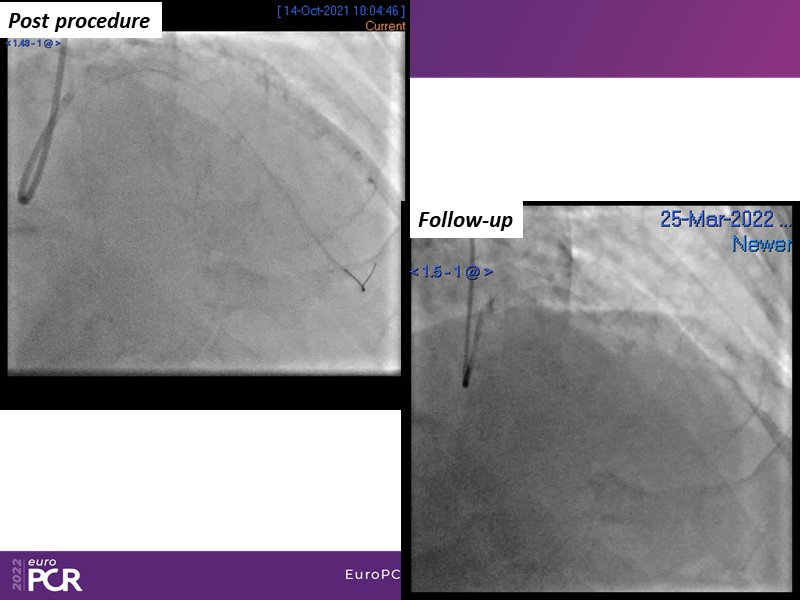

- To find out more about the application and mechanism of a sirolimus coated balloon for coronary artery disease treatment with case presentations in complex settings

- To understand how useful is a DES and DCB stent platform in complex coronary artery disease settings with case demonstrations and follow-up in diabetes mellitus